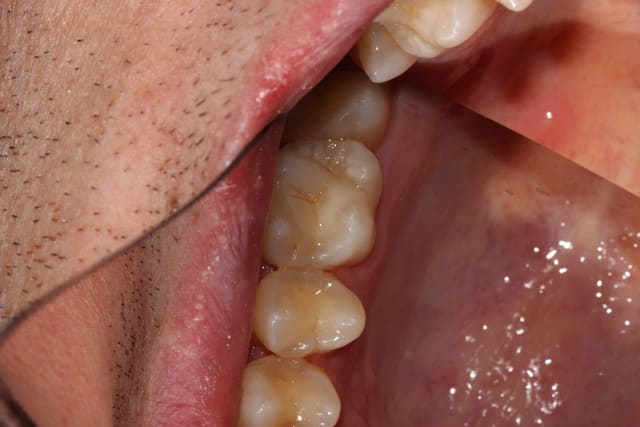

Il a été suggéré que je bossais à la zob. J'ai donc pris des photos des quelques boulots de l'aprem.

Rien de très intéressant, mais je crois avoir déjà posté un certain nombre de cas ici, tous critiquables mais aucun bâclé.

Pour ceux qui n'ont que ça à foutre, vous pouvez les relier aux posts précédents.